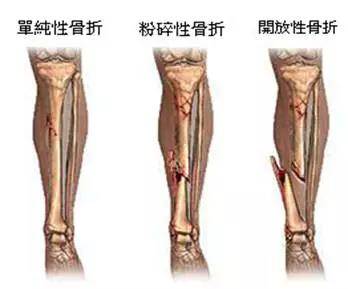

1 ã€å¤–伤骨头——粗看X线片,细看CTï¼Œæ ¸ç£çœ‹ä¸æ¸…

å„ç§å¤–伤,如果怀疑伤到了骨头,优先选择X光照片,检查结果快速易得。若è¦è¿›ä¸€æ¥è§‚察,å¯ä»¥é€‰æ‹©CTã€‚è¶…å£°ã€æ ¸ç£å¯¹äºŽéª¨çš®é«“è´¨ç‰çœ‹ä¸æ¸…,一般ä¸é€‰æ‹©ã€‚